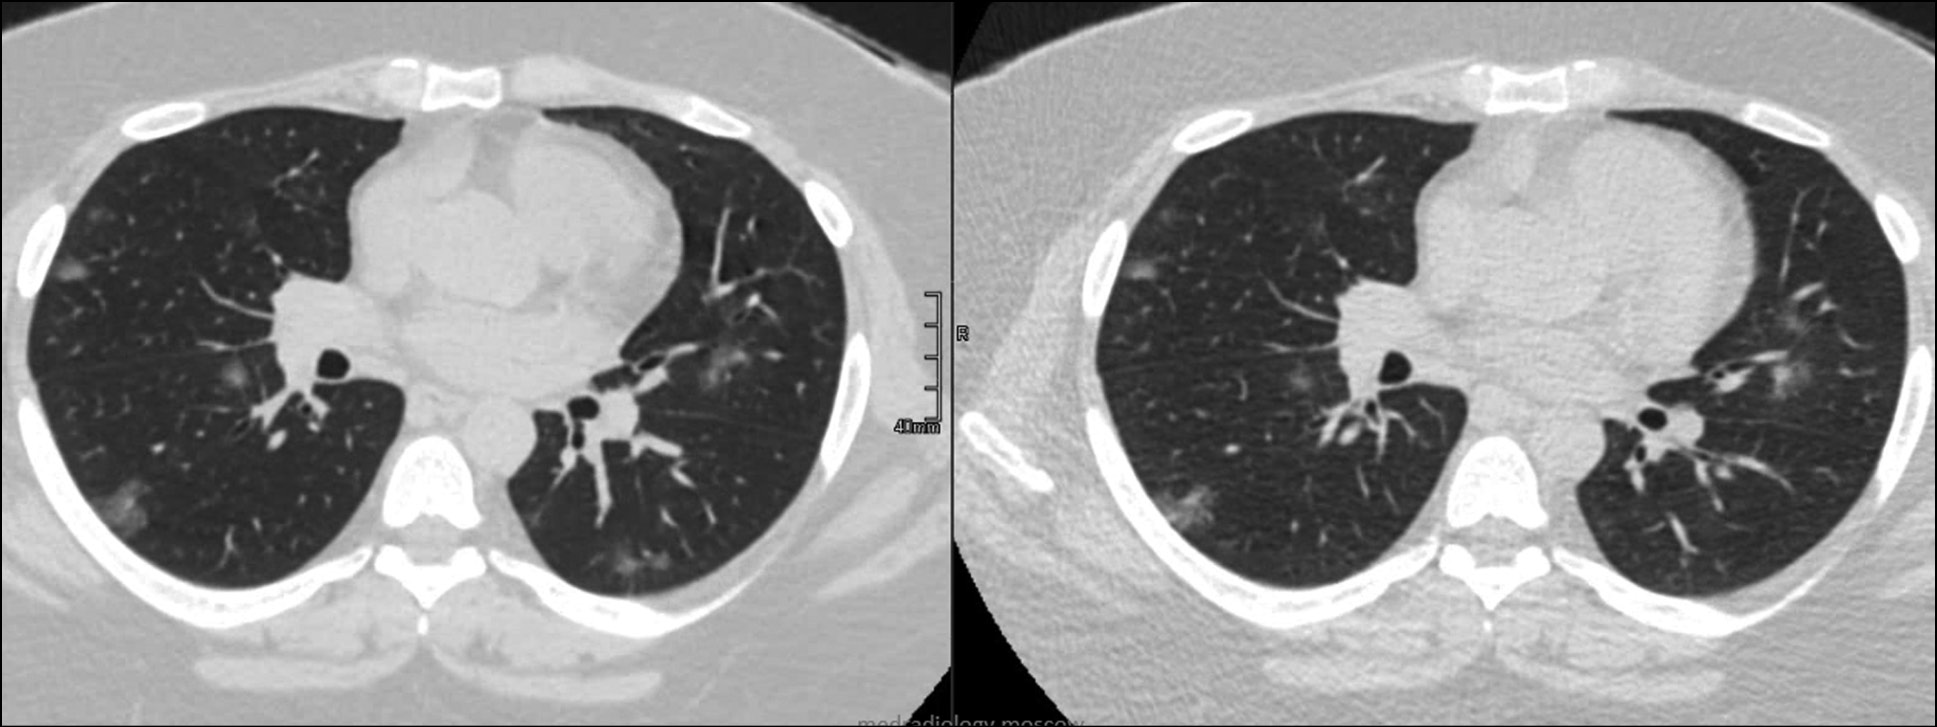

Any special low-dose protocols require clinical validation and comparison with the gold standard. Therefore, clinical trials of the developed LDCT protocol for COVID-19 used standard CT as a reference technique. [28] Some of the clinical images obtained using the developed protocol are shown in Figs. 2 and 3.

Figure 3. Radiation exposure is reduced by 1.5 times. Patient, 44 y. o., BMI 46 kg/m2. Computed tomography with a soft tissue filter (effective dose: 15.3 mSv), low-dose computed tomography with a soft tissue filter (effective dose: 10.5 mSv). Bilateral peripheral ground-glass lesions.